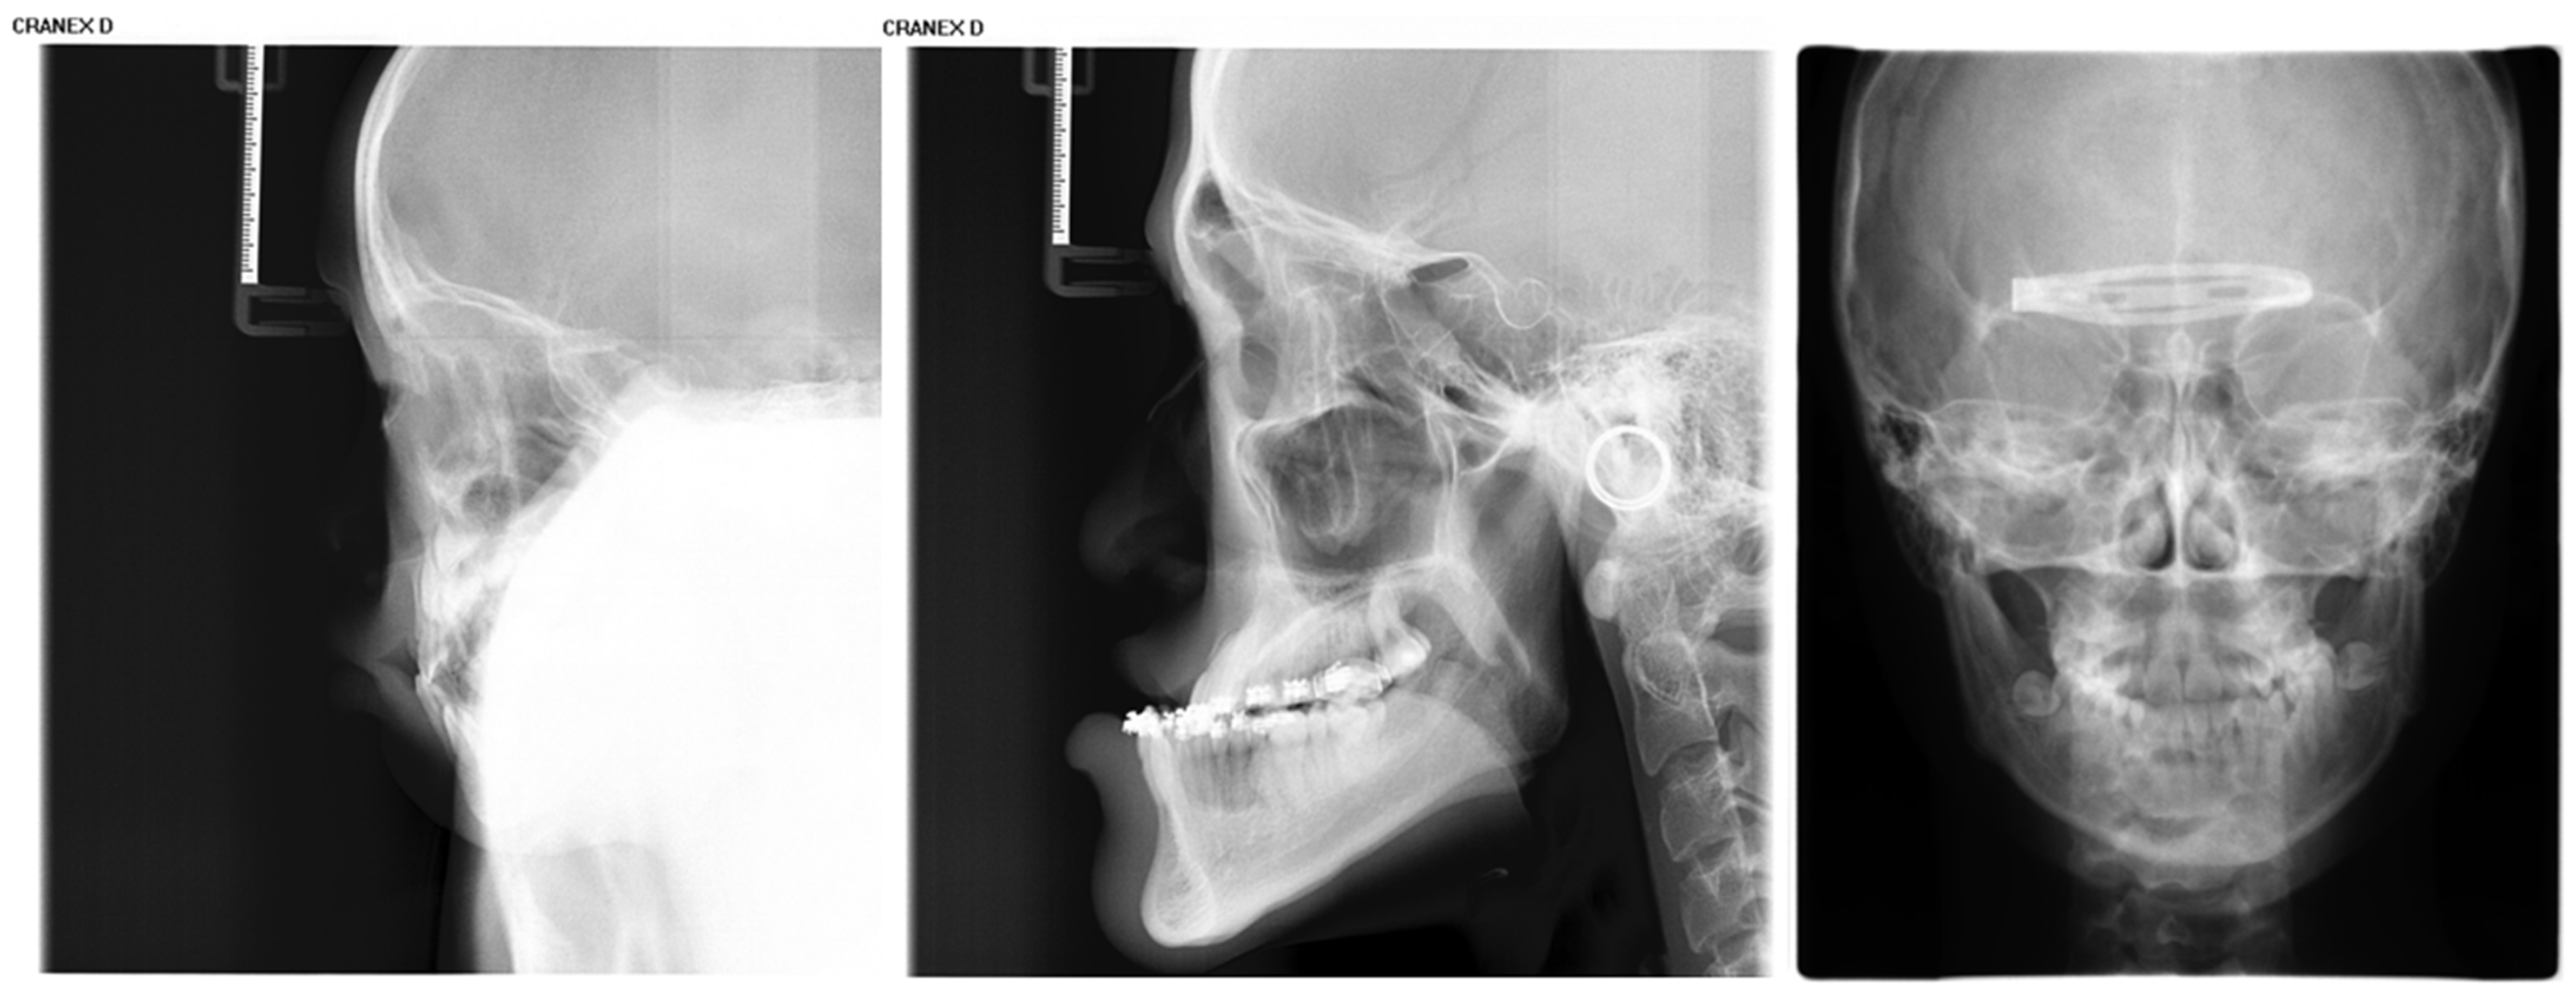

Inclusion criteria were as follows: (1) age between 4 and 18 years (up to and including 18.99 years); (2) absence of visible dental restorations in the oral cavity; (3) no substantial loss of craniofacial or dental tissues in the included samples. The LCR samples used in this study are shown in Figure 2. Exclusion criteria comprised (1) LCR images with improper positioning or incomplete anatomical coverage; (2) poor image quality resulting from blurring, underexposure, incorrect focal length, equipment malfunction, or the presence of obstructions such as metal artifacts; (3) documented history of head, facial, or neck tumors, or pathological conditions compromising bone or tooth integrity—including jaw tumors, cysts, osteomyelitis, jaw trauma, advanced periodontal disease, or tooth loss. The ineligible samples in this study are illustrated in Figure 3.

Figure 2.

The LCR samples used in this study.

Figure 3.

Illustration of ineligible lateral cephalometric radiograph samples included in this study, encompassing cases with occlusions, metallic artifacts, and content errors.